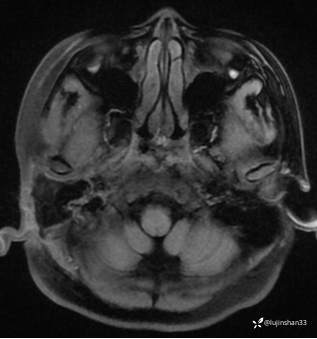

颞骨MRI:

临床诊断:1.右侧岩部胆脂瘤 2.外耳道耵聍癌术后(右)